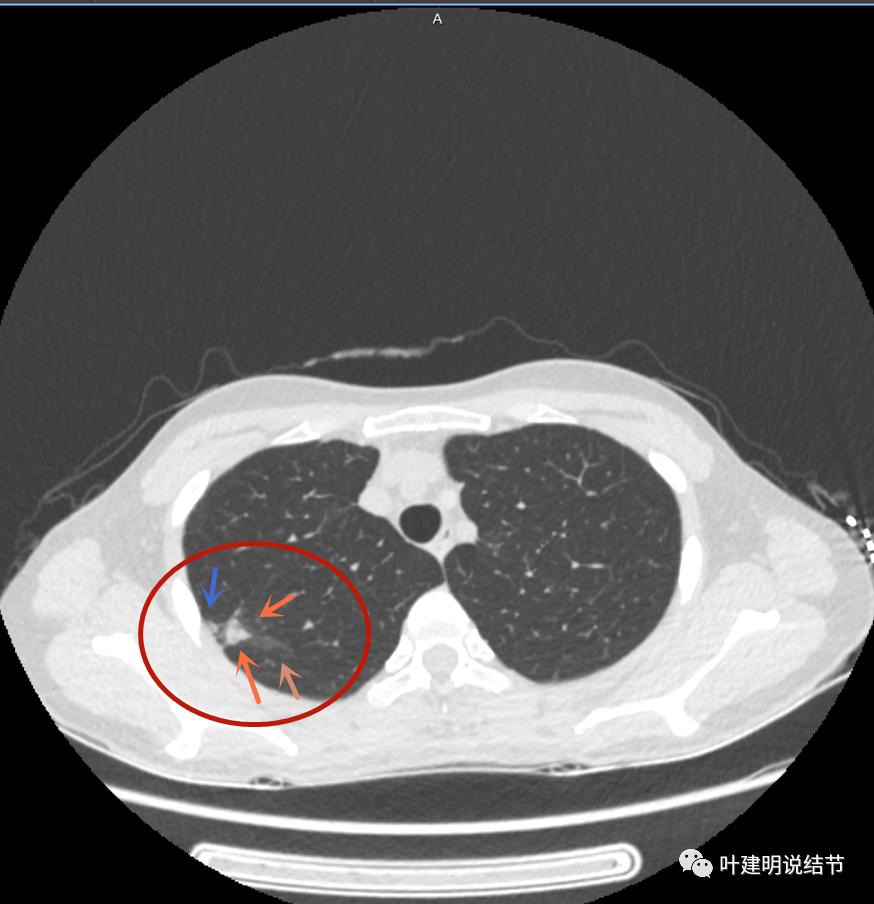

上图病灶的边相对比较光,没有毛刺征,邻近胸膜增厚

上图病灶边缘比较平直,没有膨胀性(桔色箭头),旁边的磨玻璃影淡且界限不清,邻近胸膜增厚。

再看影像印象:病灶较1年前有所进展,部分层面像恶性,囊壁厚薄不均,内面有小突起。但邻近胸膜增厚,旁边的磨玻璃部分散且淡,边界不清,实性部分边相对较光,囊壁有点状过高密度。良性可能性大些,恶性不能除外。